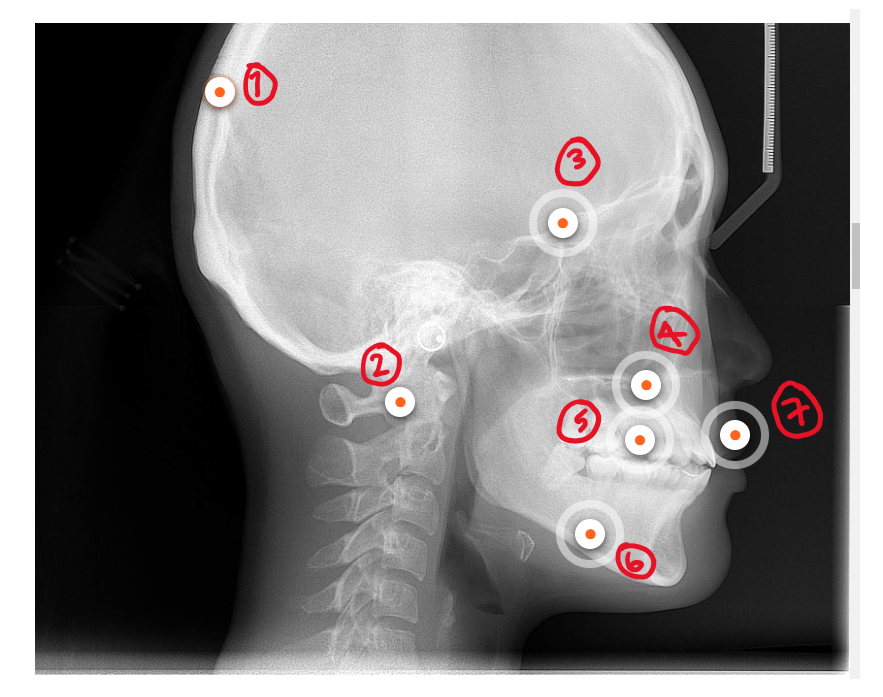

What’s 1?

Soft tissue nasion

The midpoint on the soft tissue contour of the base of the nasal root at the level of the frontonasal suture

What’s 2?

Nasion

What’s 3?

Orbitale

What’s 4?

Nasal tip

What’s 5?

Columella

Point on the lower surface of the nose, determining the anterior limit of the nasolabial angle

Q

Sella

The midpoint of the sella turcica (turkish saddle)

What’s 7?

Articulare

the intersection of the posterior border of the mandible and the lower margin of the cranial base